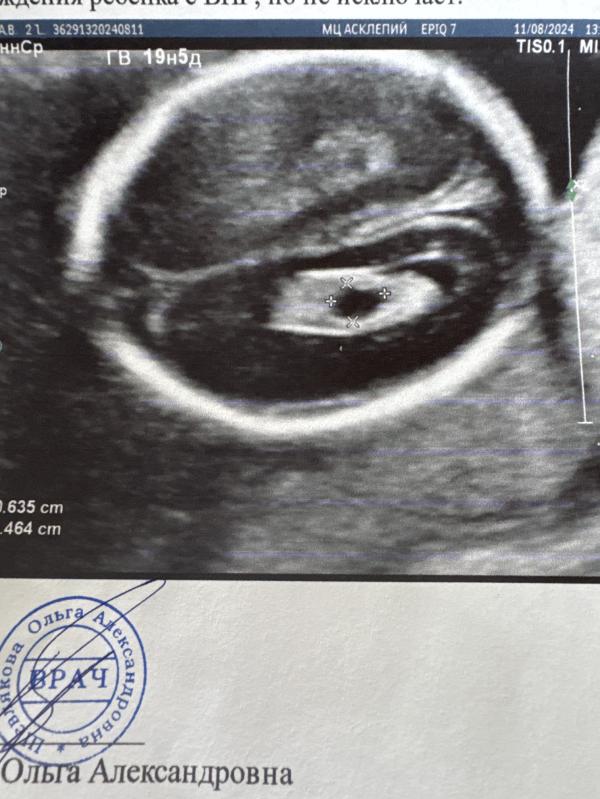

«Особенности строения плода: наличие эхо-маркеров ХА в правом сосудистом сплетении округлый анэхогенный участок 6,4х4,6 мм, с четким ровным контуром. В левом сосудистом сплетении не выраженный подобный участок 3,6х2,9 мм.» - Описание врача.